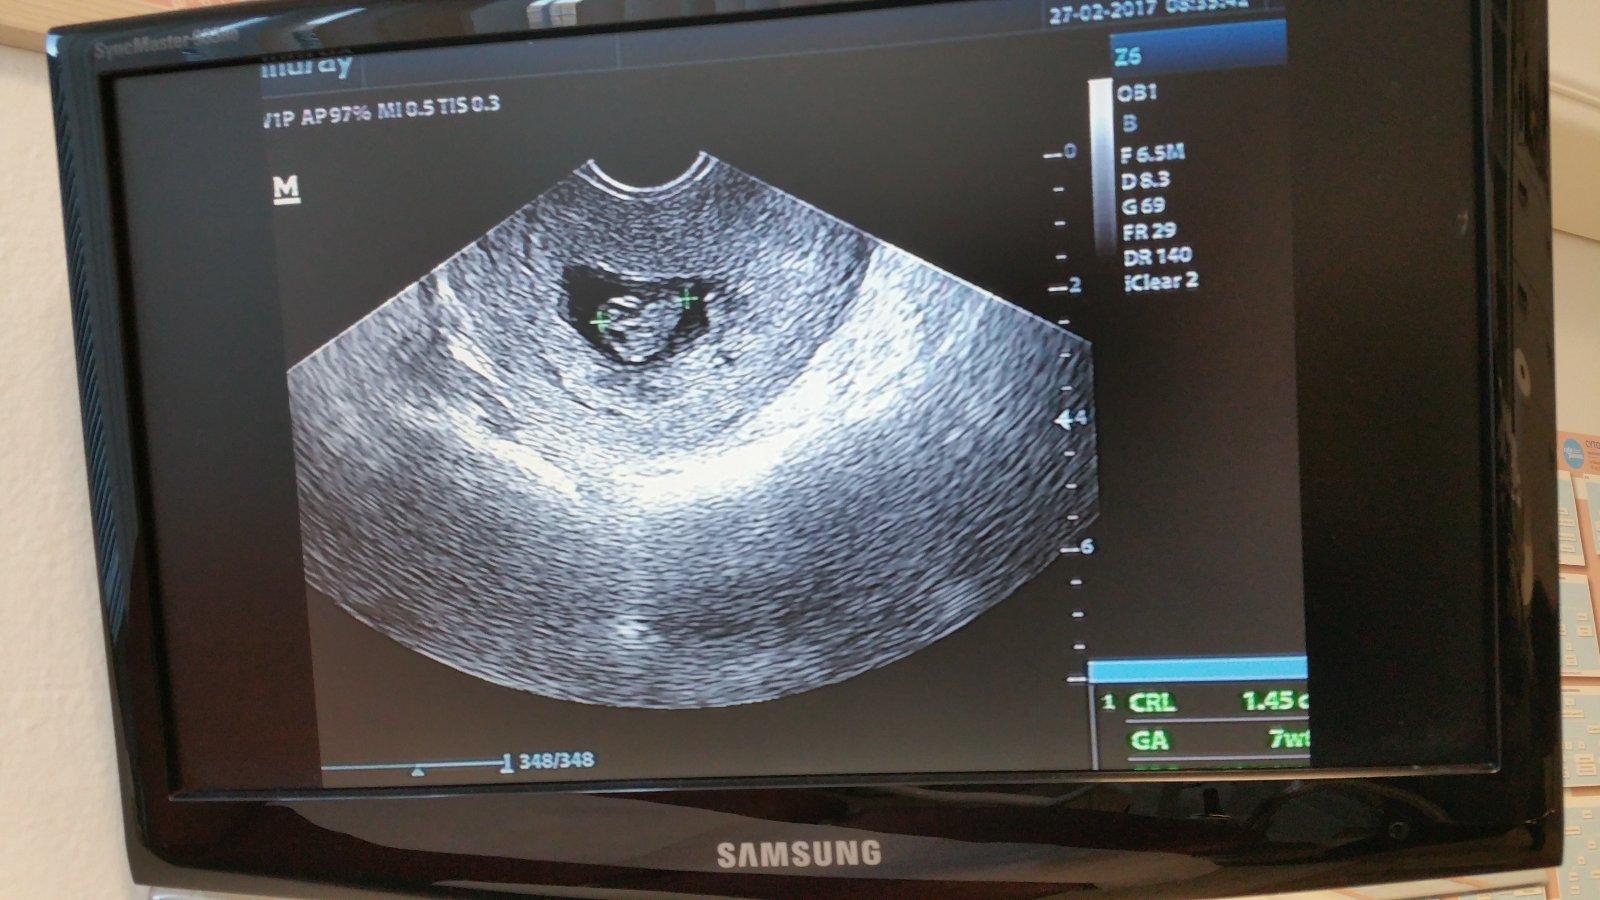

@vanda12345 ahoj pisala som do skupiny duch na teste. Tak sme 8tt+1. Srdiecko krasne bilo. 27.3. mam kontrolu a mali by sme uz dostat tehu knizku.